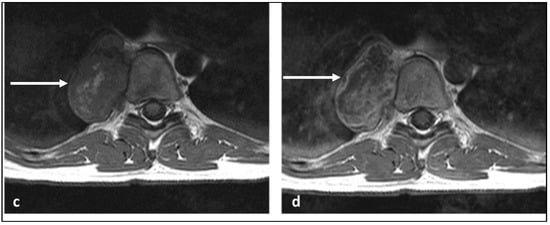

| Chondrosarcoma | Lytic lesion. ‘Rings and arcs’ calcification characteristic of chondroid matrix. | High T2 signal due to cartilage and myxoid content. Peripheral and septal enhancement. Enhancing extra-osseous soft tissue component. |